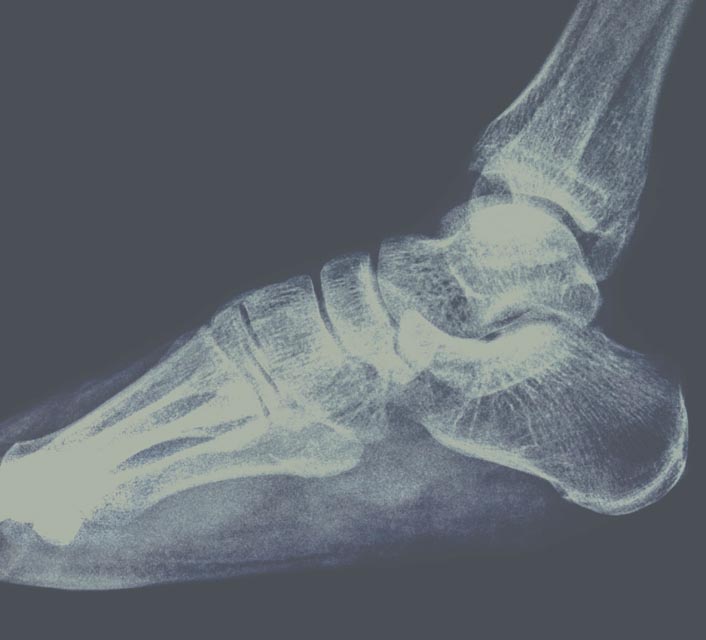

Onderzoek van uw voet middels moderne beeldvorming.

Echografisch onderzoek

Een echografisch onderzoek levert sneller en meer informatie op binnen de diagnostiek van het bewegingsapparaat.